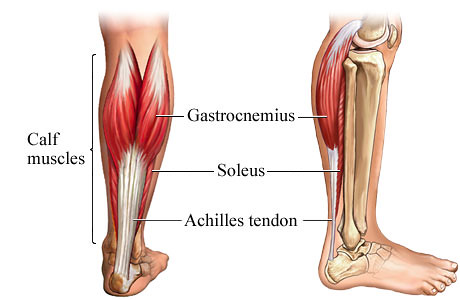

Anatomy

| Origin | Lateral head: Posterolateral aspect of lateral condyle of the femur Medial head: Posterior surface of medial femoral condyle, popliteal surface of femoral shaft |

| Insertion | Posterior surface of the calcaneus via the calcaneal tendon |

| Innervation | Tibial nerve (S1, S2) |

| Function | Talocrural joint: Foot plantar flexion Knee joint: Leg flexion |

Soleus

| Origin | Soleal line, medial border of tibia, head of fibula, posterior border of fibula |

| Insertion | Posterior surface of calcaneus (via calcaneal tendon) |

| Innervation | Tibial nerve (S1, S2) |

| Vascularization | Posterior tibial artery and vein |

| Function | Talocrural joint: Foot plantar flexion |

| Clinical relations | Soleus tear, soleus pain |